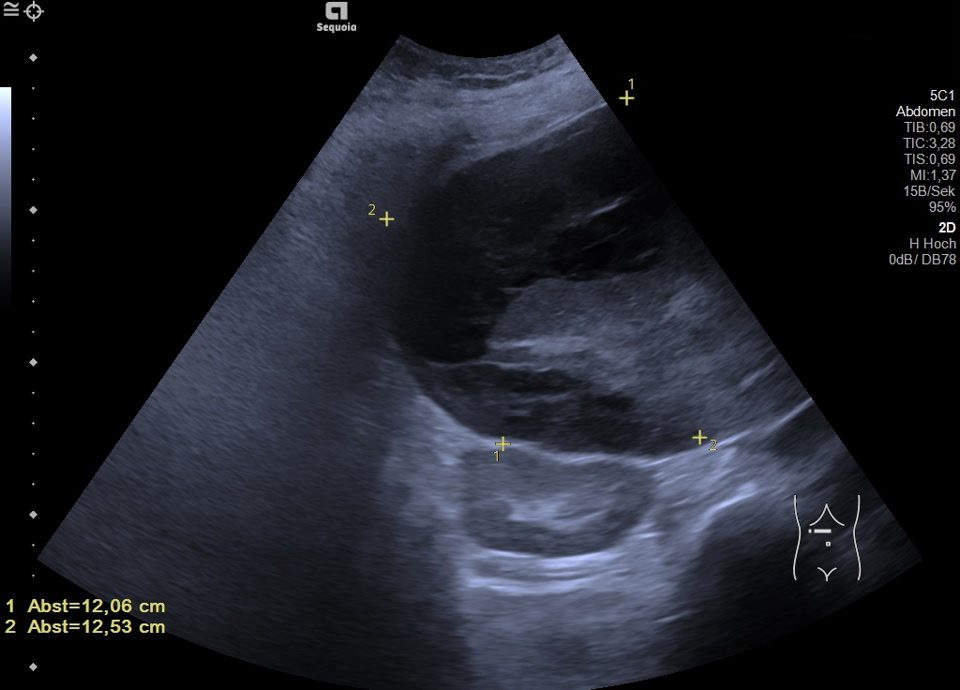

Hepatic hematoma

Intrahepatisches Hämatom und hämorrhagischer Aszites bei Zustand nach Punktion